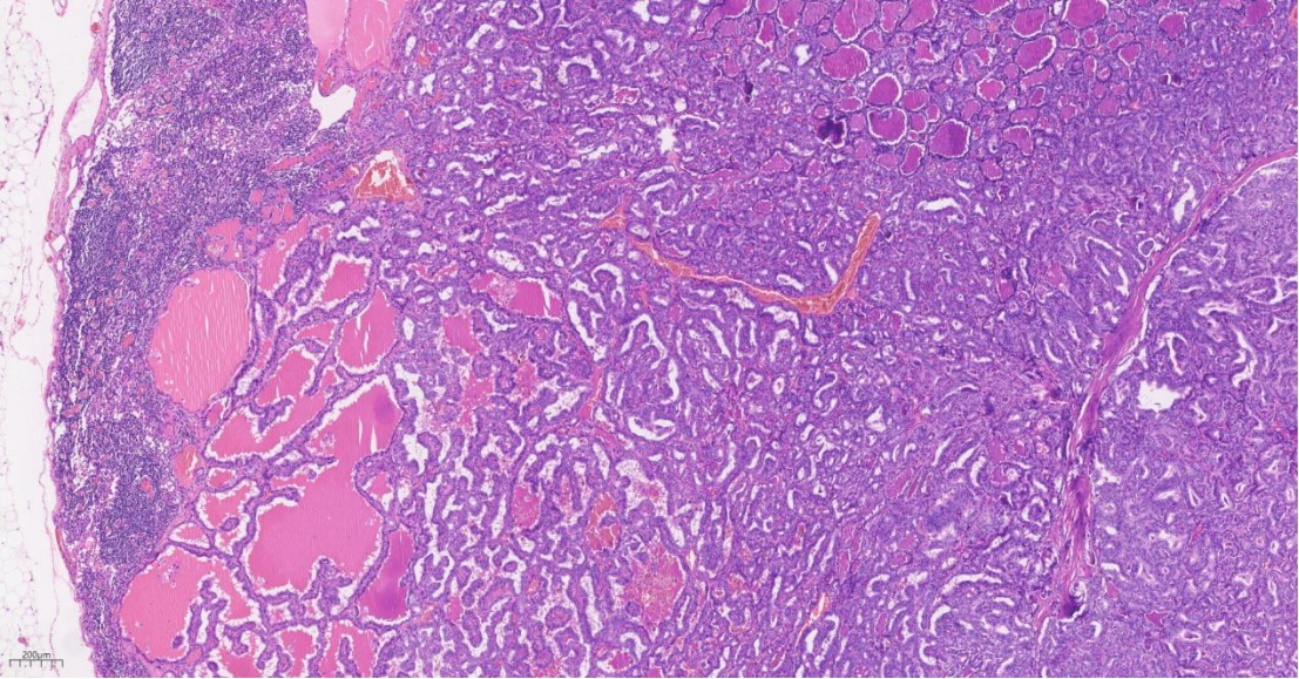

患者于2025年1月接受了双侧甲状腺全切除术以及双侧颈部II~VI区及锁骨上淋巴结清扫术。术后,对切除组织进行了详尽的病理检查及免疫组化分析,证实(左侧甲状腺)为PTC,镜下可见典型磨玻璃样核特征及核沟(图6)。其中2枚锁骨上淋巴结内可见PTC转移灶(图7),9枚锁骨上淋巴结内可见MM转移灶(图8)。术后,患者采用口服替莫唑胺与顺铂进行联合化疗。在完善BRAF V600E基因检测后,发现患者存在基因突变,随后给予甲磺酸达拉非尼和曲美替尼进行联合靶向治疗。随访1年,目前PTC暂无复发迹象,左侧乳房的MM病灶相比之前有所缩小。

Figure 8. HE staining of supraclavicular lymph node demonstrates metastatic foci of malignant melanoma

8. 锁骨上淋巴结HE染色示:可见恶性黑色素瘤转移灶